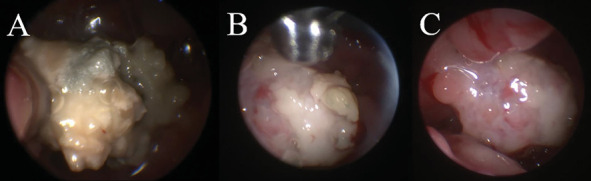

一只4岁雄性阉割混血狗被田纳西大学兽医学院兽医中心收治,以评估单侧鼻分泌物。患者出院已有2个月,在转诊前6周由兽医经验性治疗后,病情由脓性发展为出血性。狗有癫痫发作的历史,从1岁开始,用苯巴比妥控制。头部的计算机断层扫描和磁共振成像诊断为左侧脑膜脑膨出,嗅球延伸至鼻尾通道,伴有曲霉菌病的破坏性鼻炎和额窦炎。进行鼻镜检查以收集诊断样本,清除真菌斑块,并指导克霉唑乳膏的应用。活检显示化脓性鼻炎伴大量曲霉病,真菌培养证实为曲霉属。术后给予短疗程口服泊沙康唑治疗。治疗后4个月出现剧烈呼吸。复查鼻窦镜和鼻镜发现左鼻腔有一个真菌斑块,鼻甲小,充血。反复治疗,临床症状得到缓解。1个月后复查鼻镜未见残留病变。癫痫在第二次治疗后3年复发,由初级保健兽医进行医学处理。这个病例报告描述了一个罕见的病例鼻曲霉病并发脑膜膨出。尽管大筛网板缺损导致脑膜和嗅球暴露,但该患者对反复清创和局部抗真菌治疗耐受良好。3年无复发迹象,此后犬失去随访。

A 4-year-old male castrated mixed breed dog was admitted to the Veterinary Medical Center of the University of Tennessee College of Veterinary Medicine for evaluation of unilateral nasal discharge. Discharge had been present for 2 months, with progression from purulent to hemorrhagic discharge after empiric treatment by the primary veterinarian 6 weeks prior to referral. The dog had a history of seizures starting at 1 year of age that were controlled with phenobarbital. Computed tomography and magnetic resonance imaging of the head yielded diagnoses of a left-sided meningoencephalocele with extension of the olfactory bulb into the caudal nasal passage and destructive rhinitis and frontal sinusitis consistent with aspergillosis. Rhinoscopy was performed to collect diagnostic samples, debride fungal plaques, and guide clotrimazole cream application. Biopsies revealed suppurative rhinitis with abundant aspergillosis, with Aspergillus sp. confirmed on fungal culture. Postoperatively, the patient was treated with a short course of oral posaconazole. Stertorous breathing was noted 4 months following treatment. Recheck sinoscopy and rhinoscopy revealed one fungal plaque in the left nasal cavity and small, hyperemic turbinates. Treatment was repeated, resulting in resolution of clinical signs. Repeat rhinoscopy 1 month later had no evidence of residual disease. Seizures recurred 3 years after the second treatment and were medically managed by the primary care veterinarian. This case report describes a rare case of nasal aspergillosis complicated by a meningoencephalocele. Despite the large cribriform plate defect resulting in exposure of the meninges and olfactory bulb, repeated debridement and topical antifungal treatment were well tolerated by this patient. There was no recurrence in signs for 3 years, after which the dog was lost to follow-up.